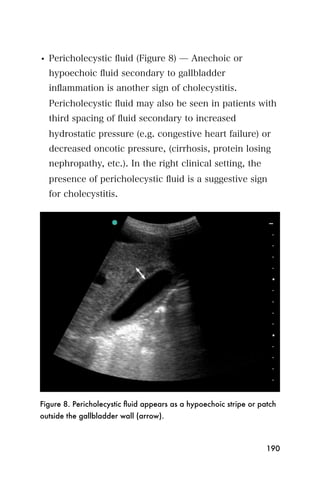

The probe marker should point to the patient s head or

the patient s right side.

Visualizing the spleen

The echo pattern of the spleen is smooth and

homogenous and slightly darker than liver. The